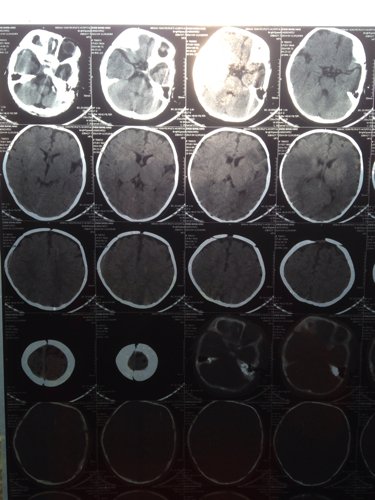

宝宝出生时被诊断为轻度缺血缺氧性脑病,住院治疗一个疗程,现在宝宝5个月复查做了CT,麻烦专业人士给

宝宝出生时被诊断为轻度缺血缺氧性脑病,住院治疗一个疗程,现在宝宝5个月复查做了CT,麻烦专业人士给看看,谢谢

问题分析: 新生儿窒息很容易引起缺血缺氧性脑病,如果当时没有抽搐,肌张力正常,精神状态好的话,应该是轻度的。 意见建议: 如果有条件可以给与第二疗程的神经节苷评裕脂,这样效果好,如果没有条件,多给孩了射暖子进行康复训练,孩高究子的可塑性很大。